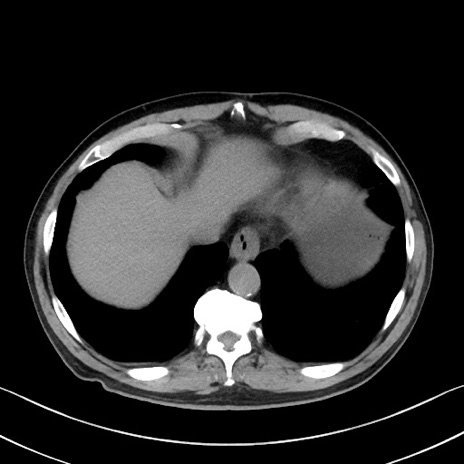

症例35(横断像)

【症例】70歳代 男性

【主訴】腹部膨満、嘔吐

【現病歴】昨日より腹部膨満感出現。本日増悪し、仙痛出現。嘔吐あり、受診。

【既往歴】糖尿病、胆摘後

【身体所見】BP 149/80mmHg、HR 74/min、BT 35.9℃、腹部:膨満、軟、圧痛なし。腸雑音減弱あり。上腹部正中切開瘢痕あり。

【データ】WBC 13500、CRP 1.72